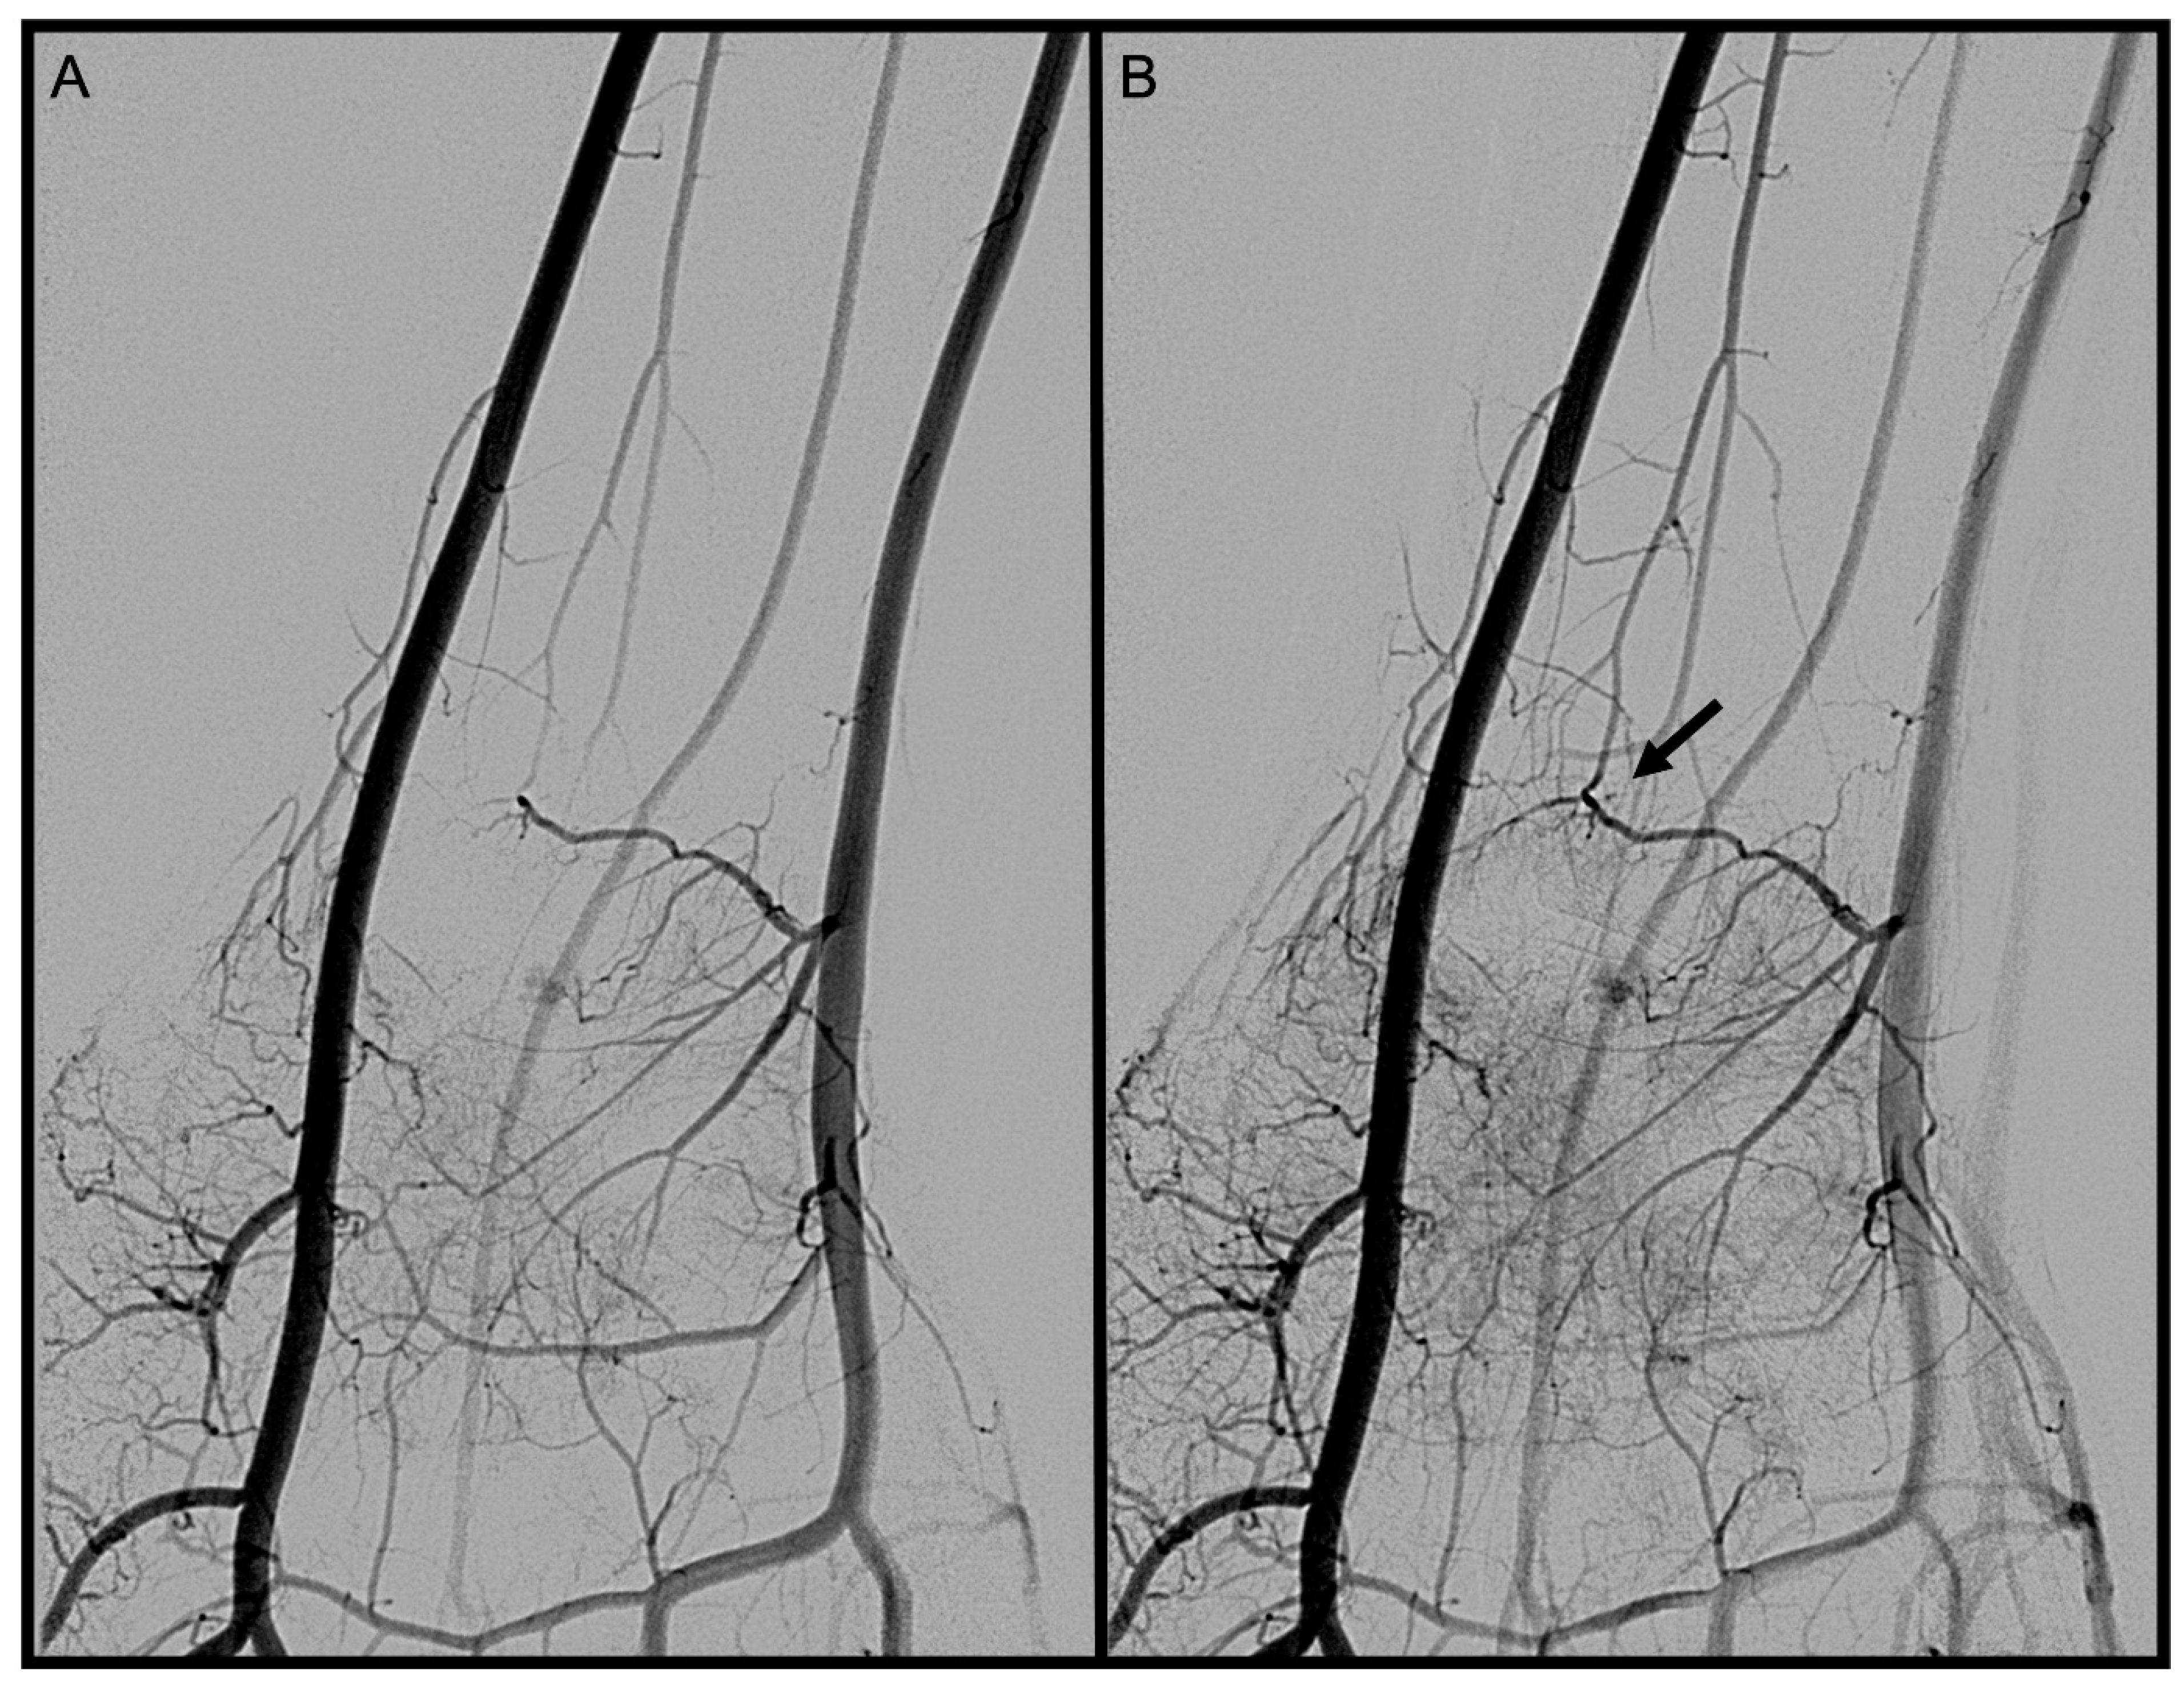

3.3. Anterior Interosseous Artery (AIA)